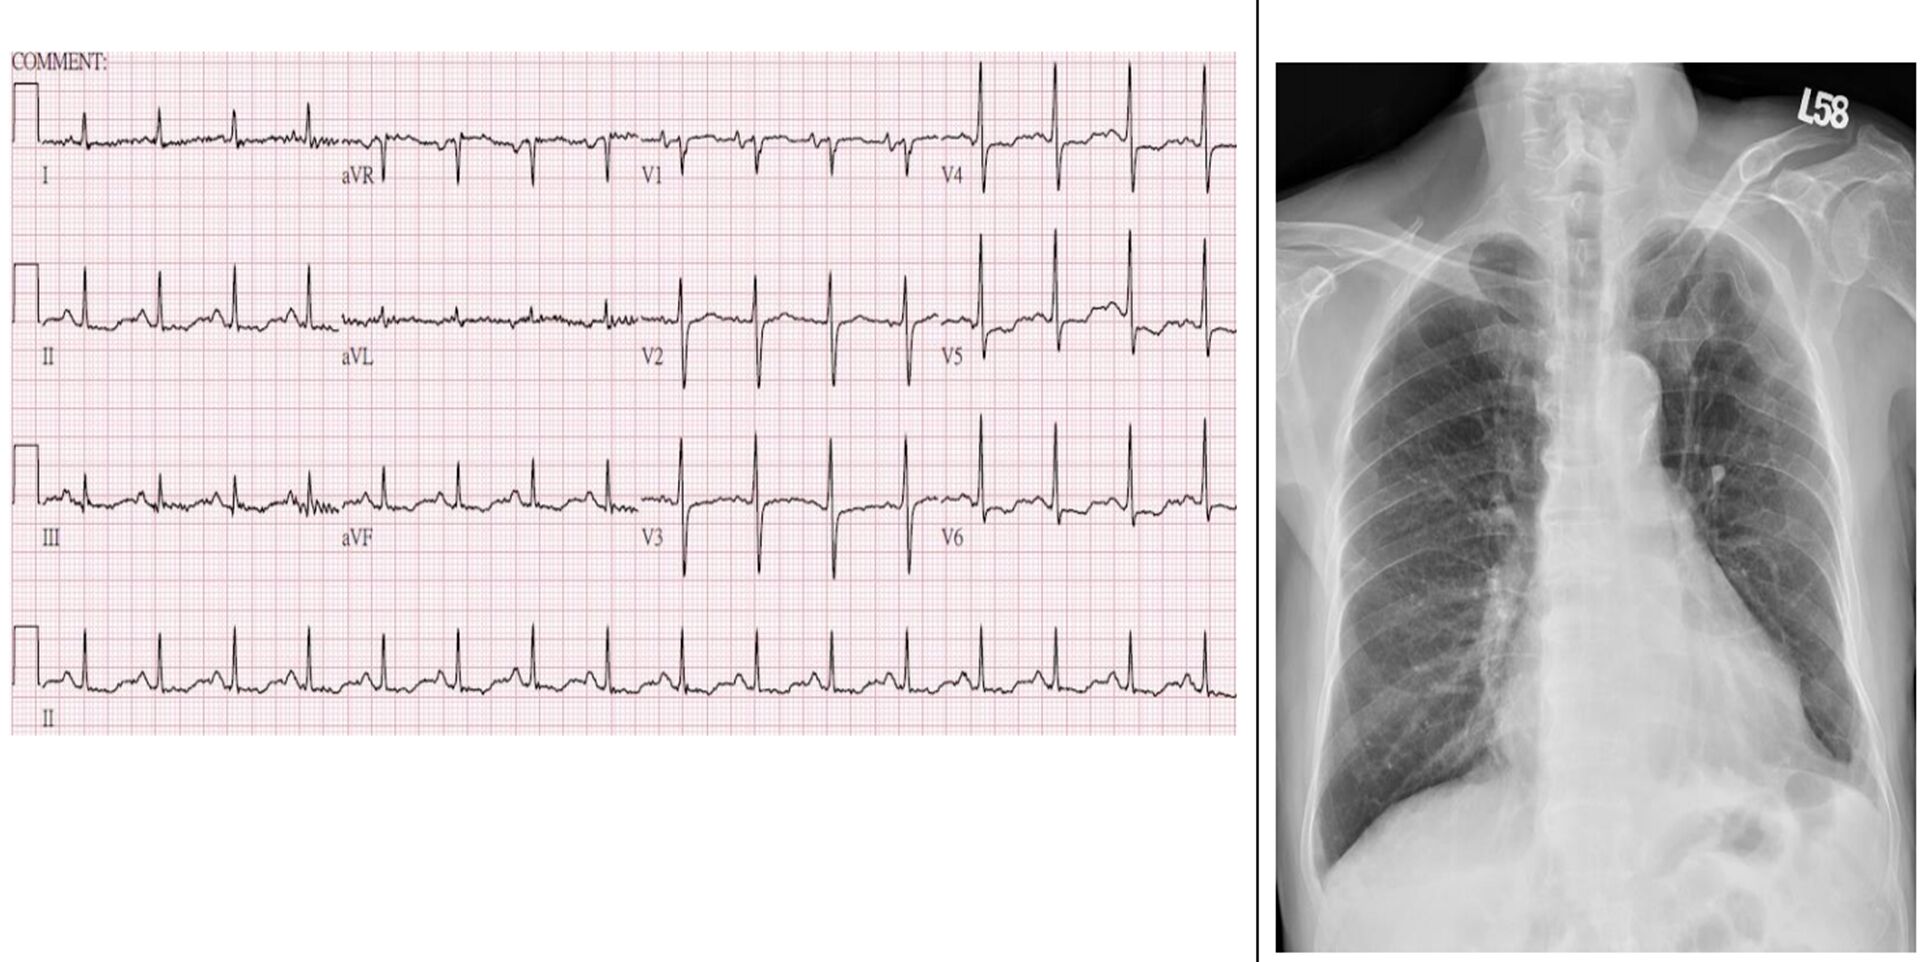

16. 一位55歲女性病患因端坐呼吸與動喘一週而來住院。身體診察發現血壓90/56毫米汞柱,心跳每分 鐘102下,頸靜脈怒張,心音低遠併第三心音,肺部有囉音,雙下肢小腿與腳部水腫。心電圖如圖一。心臟超音波呈現左心室擴大,瀰漫性左心室收縮功能異常,左心室射出分率(left ventricle ejection fraction)為25%。心臟磁振造影檢查如圖二A與B。經食道心臟超音波如圖二C與D。請問下列敘述何者錯誤?

(1)該病患的心電圖呈現 low voltage in frontal leads (2)該病患心電圖呈現心房顫動 (3)該病患之心臟磁 振造影影像檢查呈現左心室心肌緻密化不全(left ventricular non-compaction) (4)該病患之心臟磁振造影影 像檢查呈現急性心肌發炎 (5)該病患應使用口服抗凝血劑 (6)這種疾病有時是因肌節(sarcomere)基因異常 引起 (A) (1)+(3)+(6)。 (B) (2)+(3)+(5)。 (C) (2)+(4)。 (D) (2)+(4)+(5)。